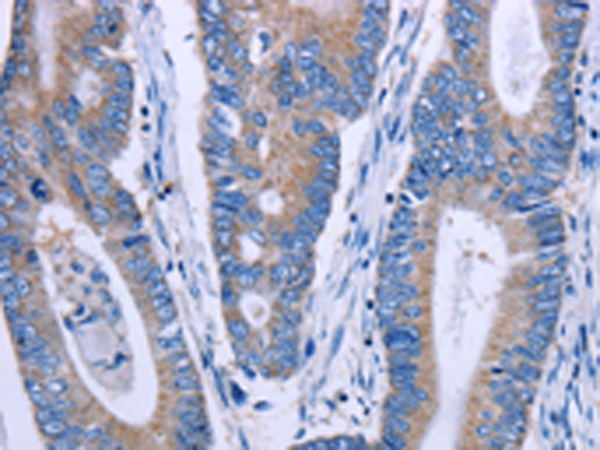

分类: 科研抗体货号: P10853别名: ALXR, HM63, FMLPX, FPR2A, FPRH1, FPRH2, FPRL1, LXA4R, FMLP-R-II应用: IHC反应种属: Human